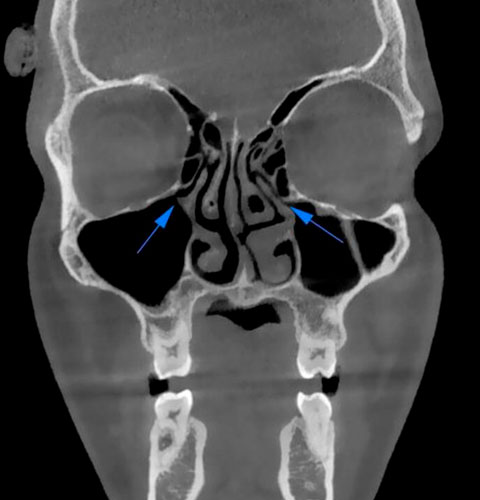

Veja exemplos de diagnósticos de imagem